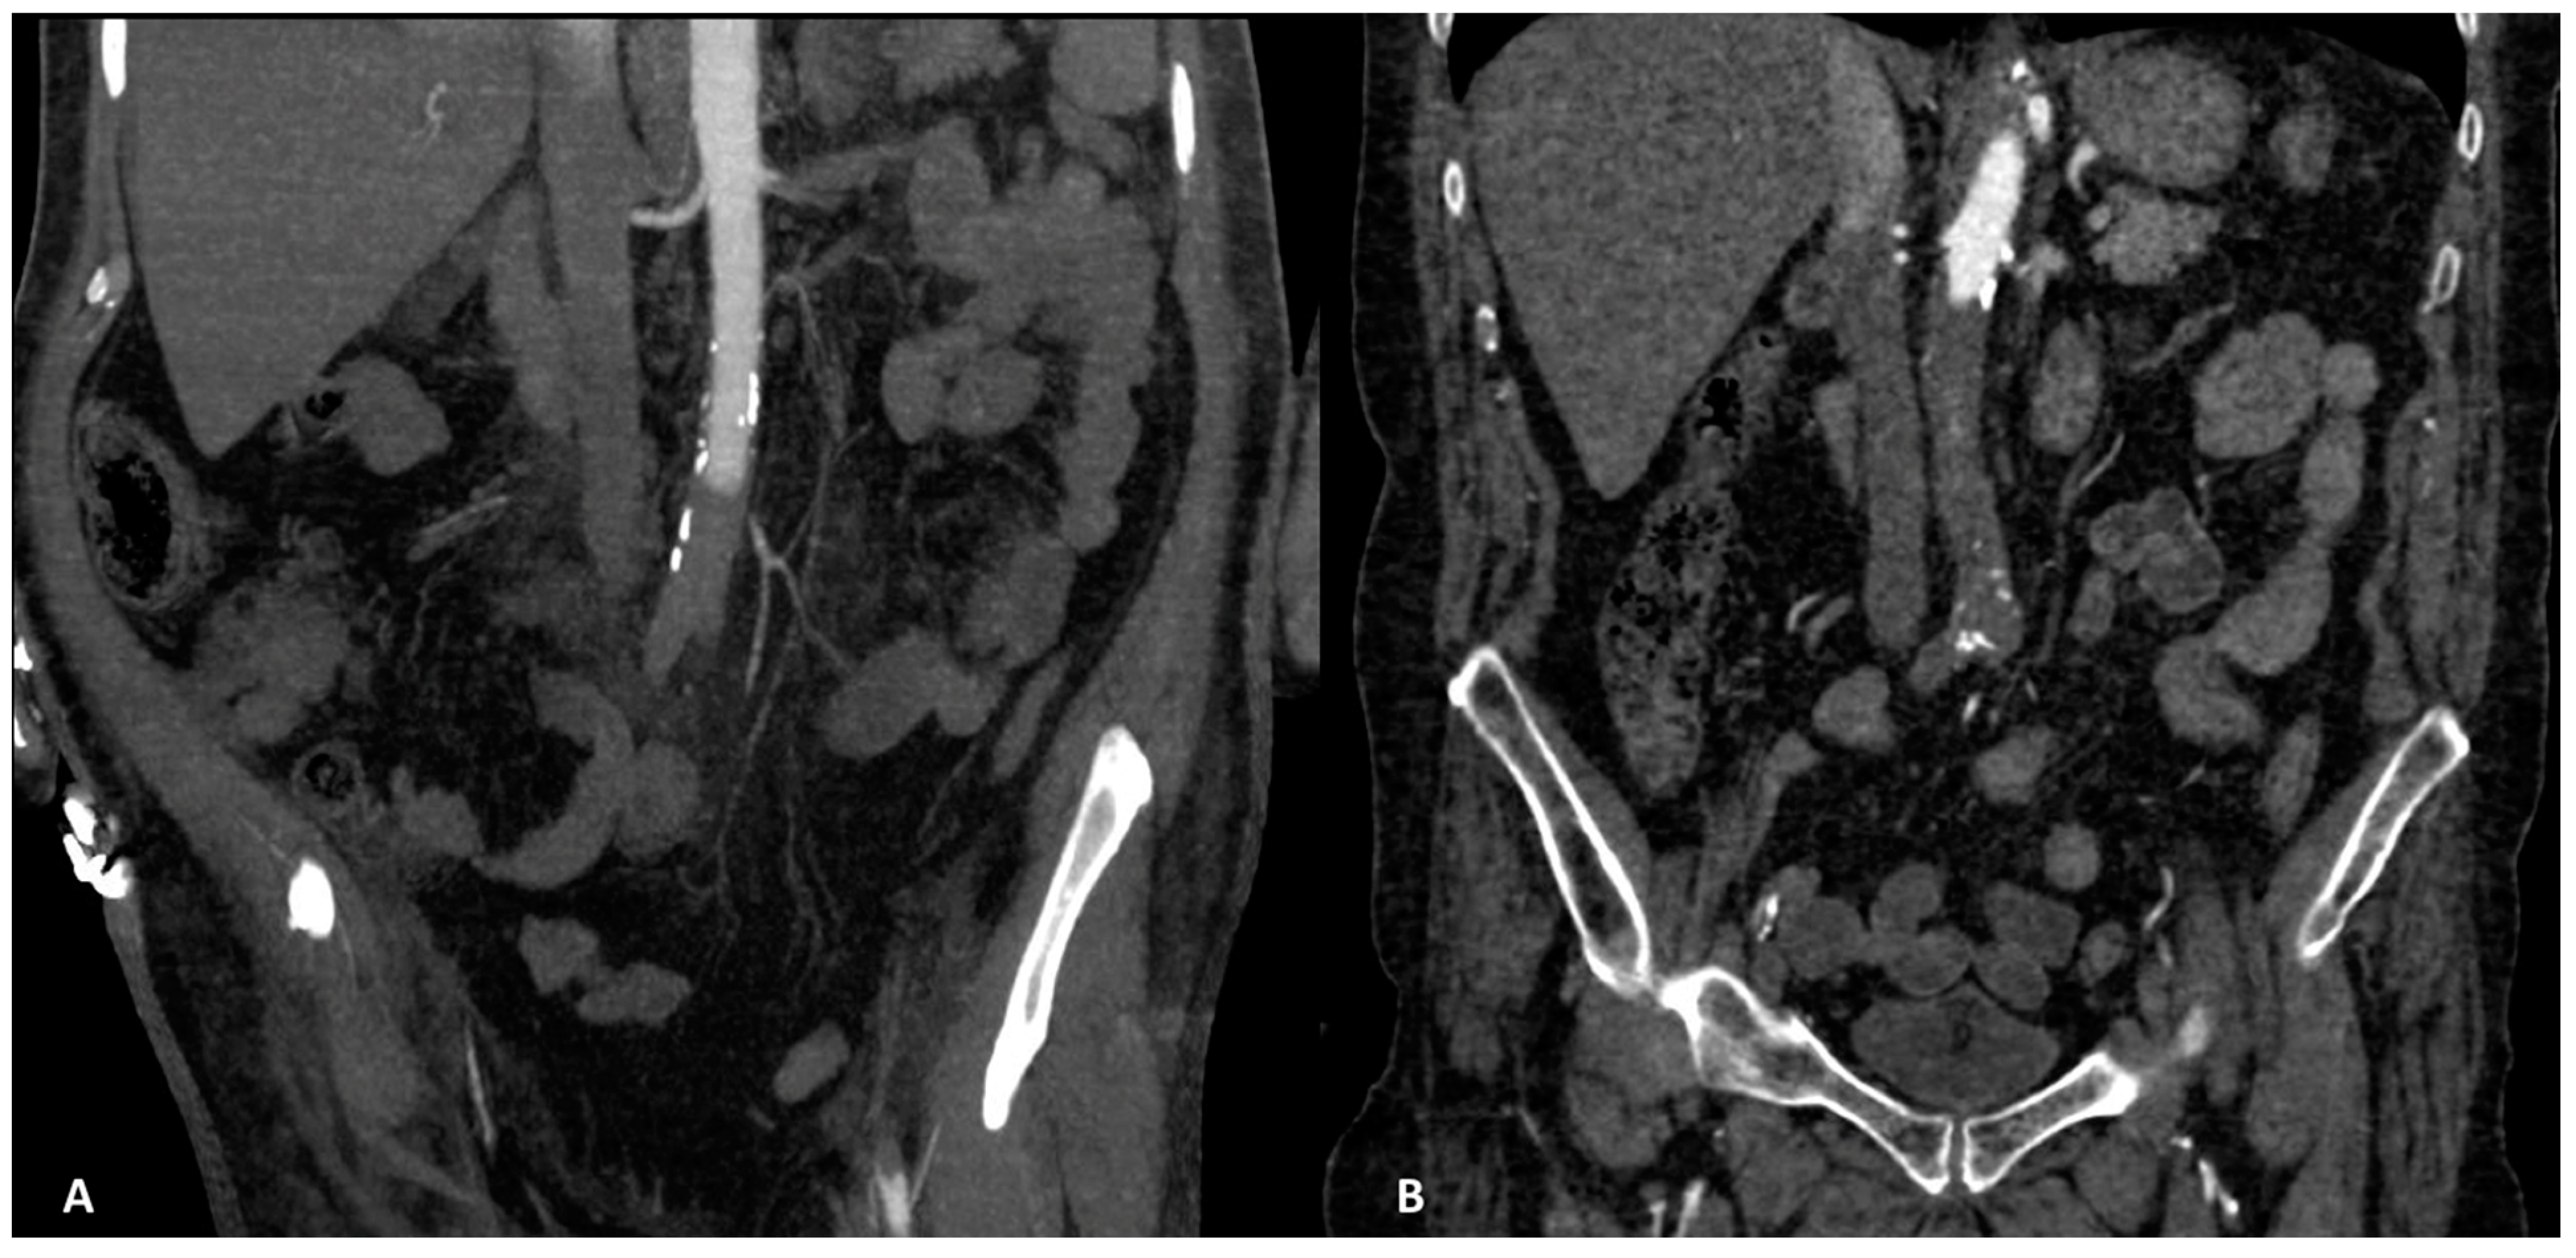

| 9/11 | Subrenal aorta to common iliac arteries bilaterally | 81.8% |

| 2/11 | Infrarenal aorta to common iliac arteries bilaterally | 18.2% |